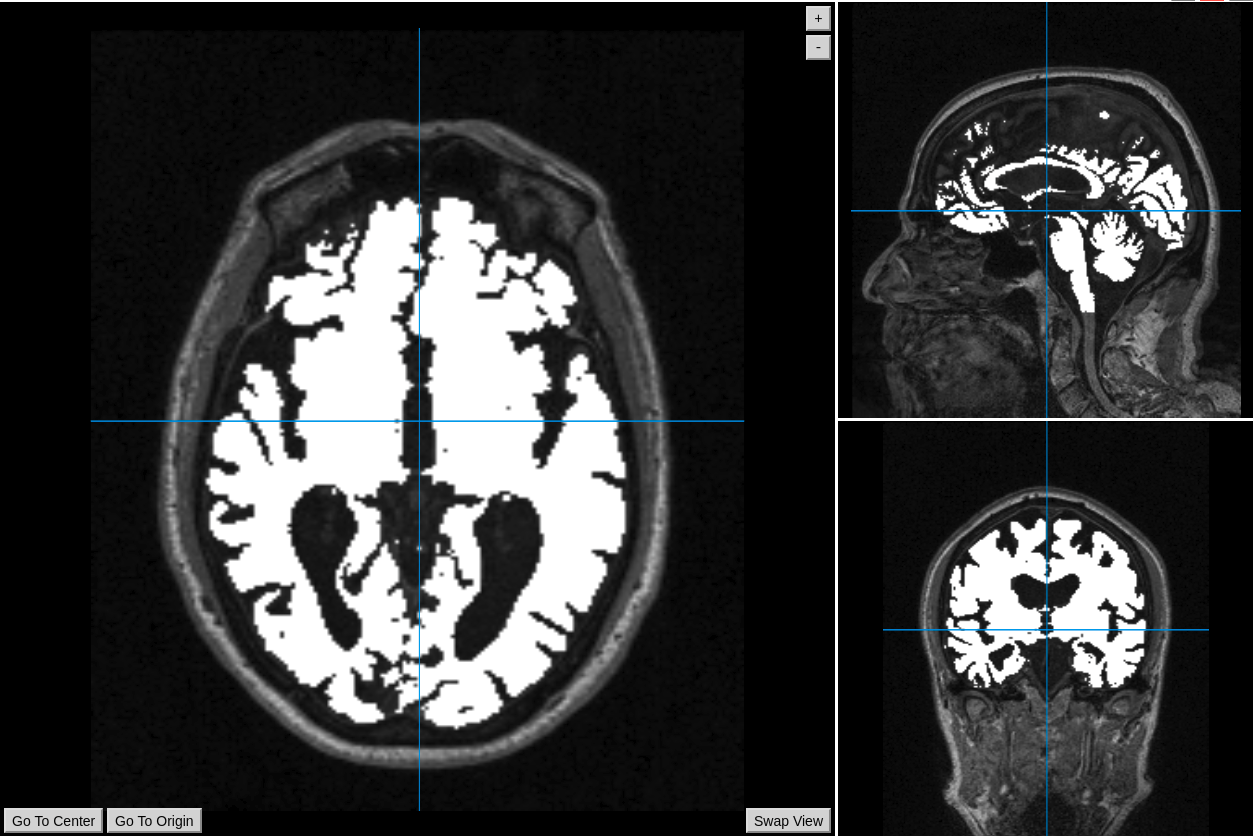

The aim is to display a brain segmentation overlapped on a T1 MRI image (both Nifti) using AMI. The problem is that the brain segmentation appears shifted from the T1. However, when I load these images with Papaya web viewer, FreeView or MRView, everything is properly registered.

Image badly registered, loaded with AMI.js (code example given just above)